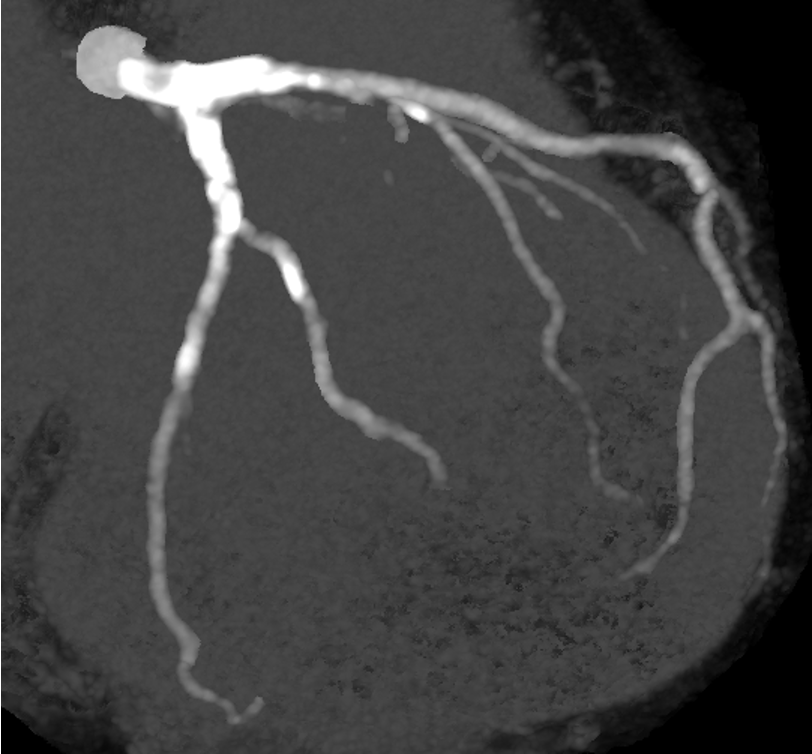

LCA CAG

-